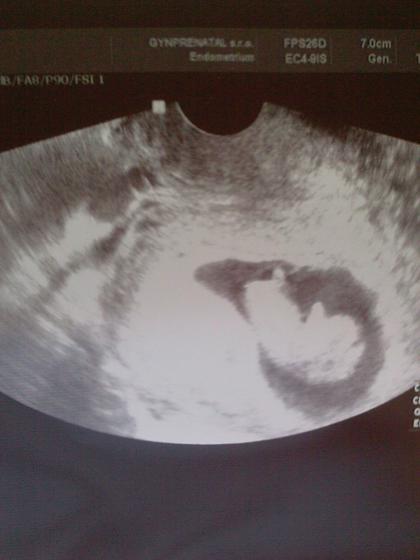

Začnu od začátku, // na testíku sem našla odpoledne 25.6 to mi ms meškala už 3 den. Poprvé k dr. sem šla 7.7.2010 těhu bylo potvrzené a měli jsme žloutkový a gestační váček to jsme byli v 5 tt. Další kontrola byla 21.7.2010 byli jsme 7+3 a srdíčko ♥ bušilo jako zvon a dostali jsme první fotečku naší tečičky. Do první poradny jsme šli 4.8.2010 to jsme byli 9+6 prcek krásně od poslední kontroly povyrostl a dostali jsme těhu průkazku a druhou fotečku termín máme dle UTZ 3.3.2011 a dle PM 2.3.2011. Druhou poradnu máme 1.9.2010

1.9 druhá poradna jsme 13+6 a měřím od hlavičky k zadečku 6 cm, Nt screening dopadl na 1* a je to na 90% klučík